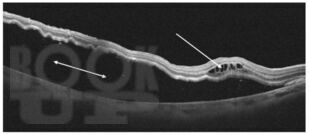

Учебное пособие содержит информацию о морфофункциональных изменениях органа зрения при нормальной беременности. Подробно описаны осложнения со стороны органа зрения на фоне патологической беременности. Приведён порядок ведения беременности и родов у женщин с заболеваниями глаз, а также при офтальмологических патологиях, связанных с развитием гестационных осложнений. Указаны изменения со стороны органа зрения, учитывающиеся при выборе способа родоразрешения.